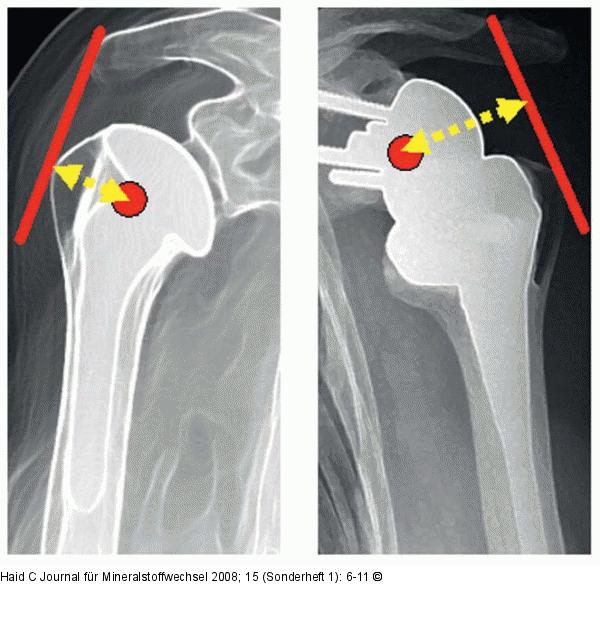

Abbildung 2: Drehmoment Beim Einsatz der inversen Prothese vergrößert sich der Hebelarm der Muskulatur. Aus diesem Grund kann mit gleicher Muskelkraft ein größeres Drehmoment erzeugt werden. |

Beim Einsatz der inversen Prothese vergrößert sich der Hebelarm der Muskulatur. Aus diesem Grund kann mit gleicher Muskelkraft ein größeres Drehmoment erzeugt werden. |